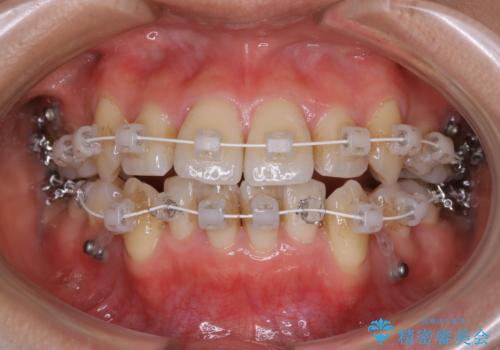

- ワイヤー(審美装置)

検査の結果、抜歯をすることでスペースを作って並べる方法が選択され、ワイヤー装置を用いた治療を開始することとなりました。

奥歯の上下のズレ等は軽度で、必要なスペースと抜歯により作られるスペースがほぼ等量だったため治療の単純化が計れ、大きな移動・見た目の劇的な変化に対して比較的早期での治療完了となりました。

- 審美装置/93万円(税込み) マイクロインプラント4本/8.8万円(税込み)費用は治療当時の料金となります